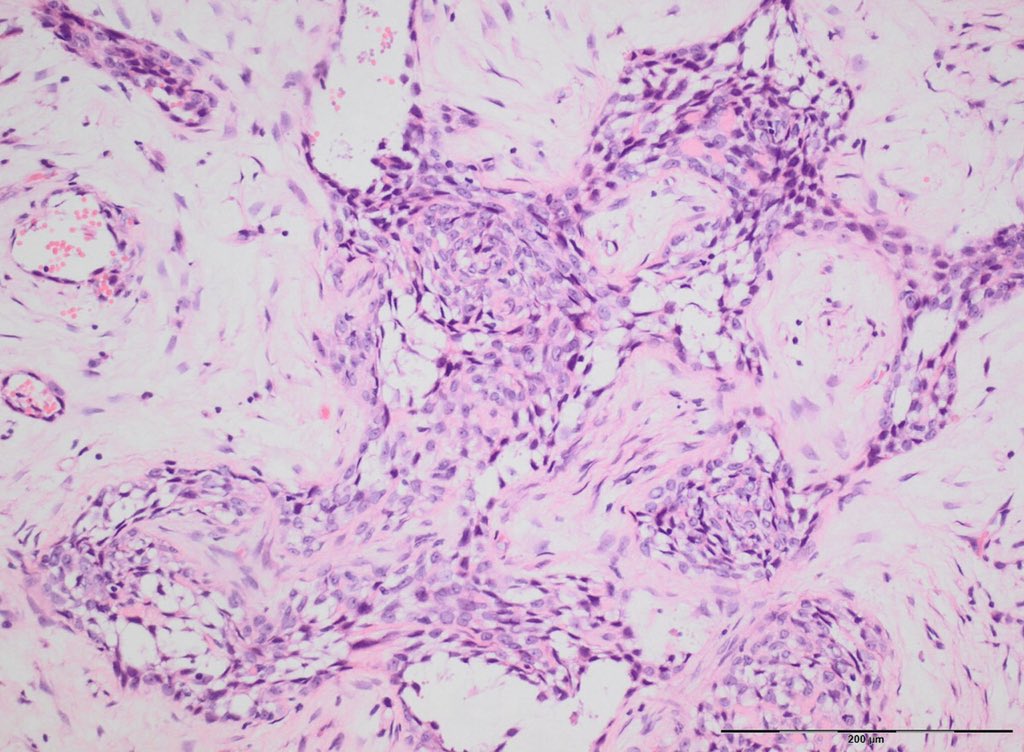

Histologically, these tumours show a biphasic pattern with epithelial or spindle cells in nests or aggregates, embedded in a paucicellular fibrous stroma.

Mitotic activity is usually low. The epithelioid component shows varied histological appearances, described as basaloid, squamous, tubular or spindle cell. The so-called differentiated / osteofibrous dysplasia-like AD